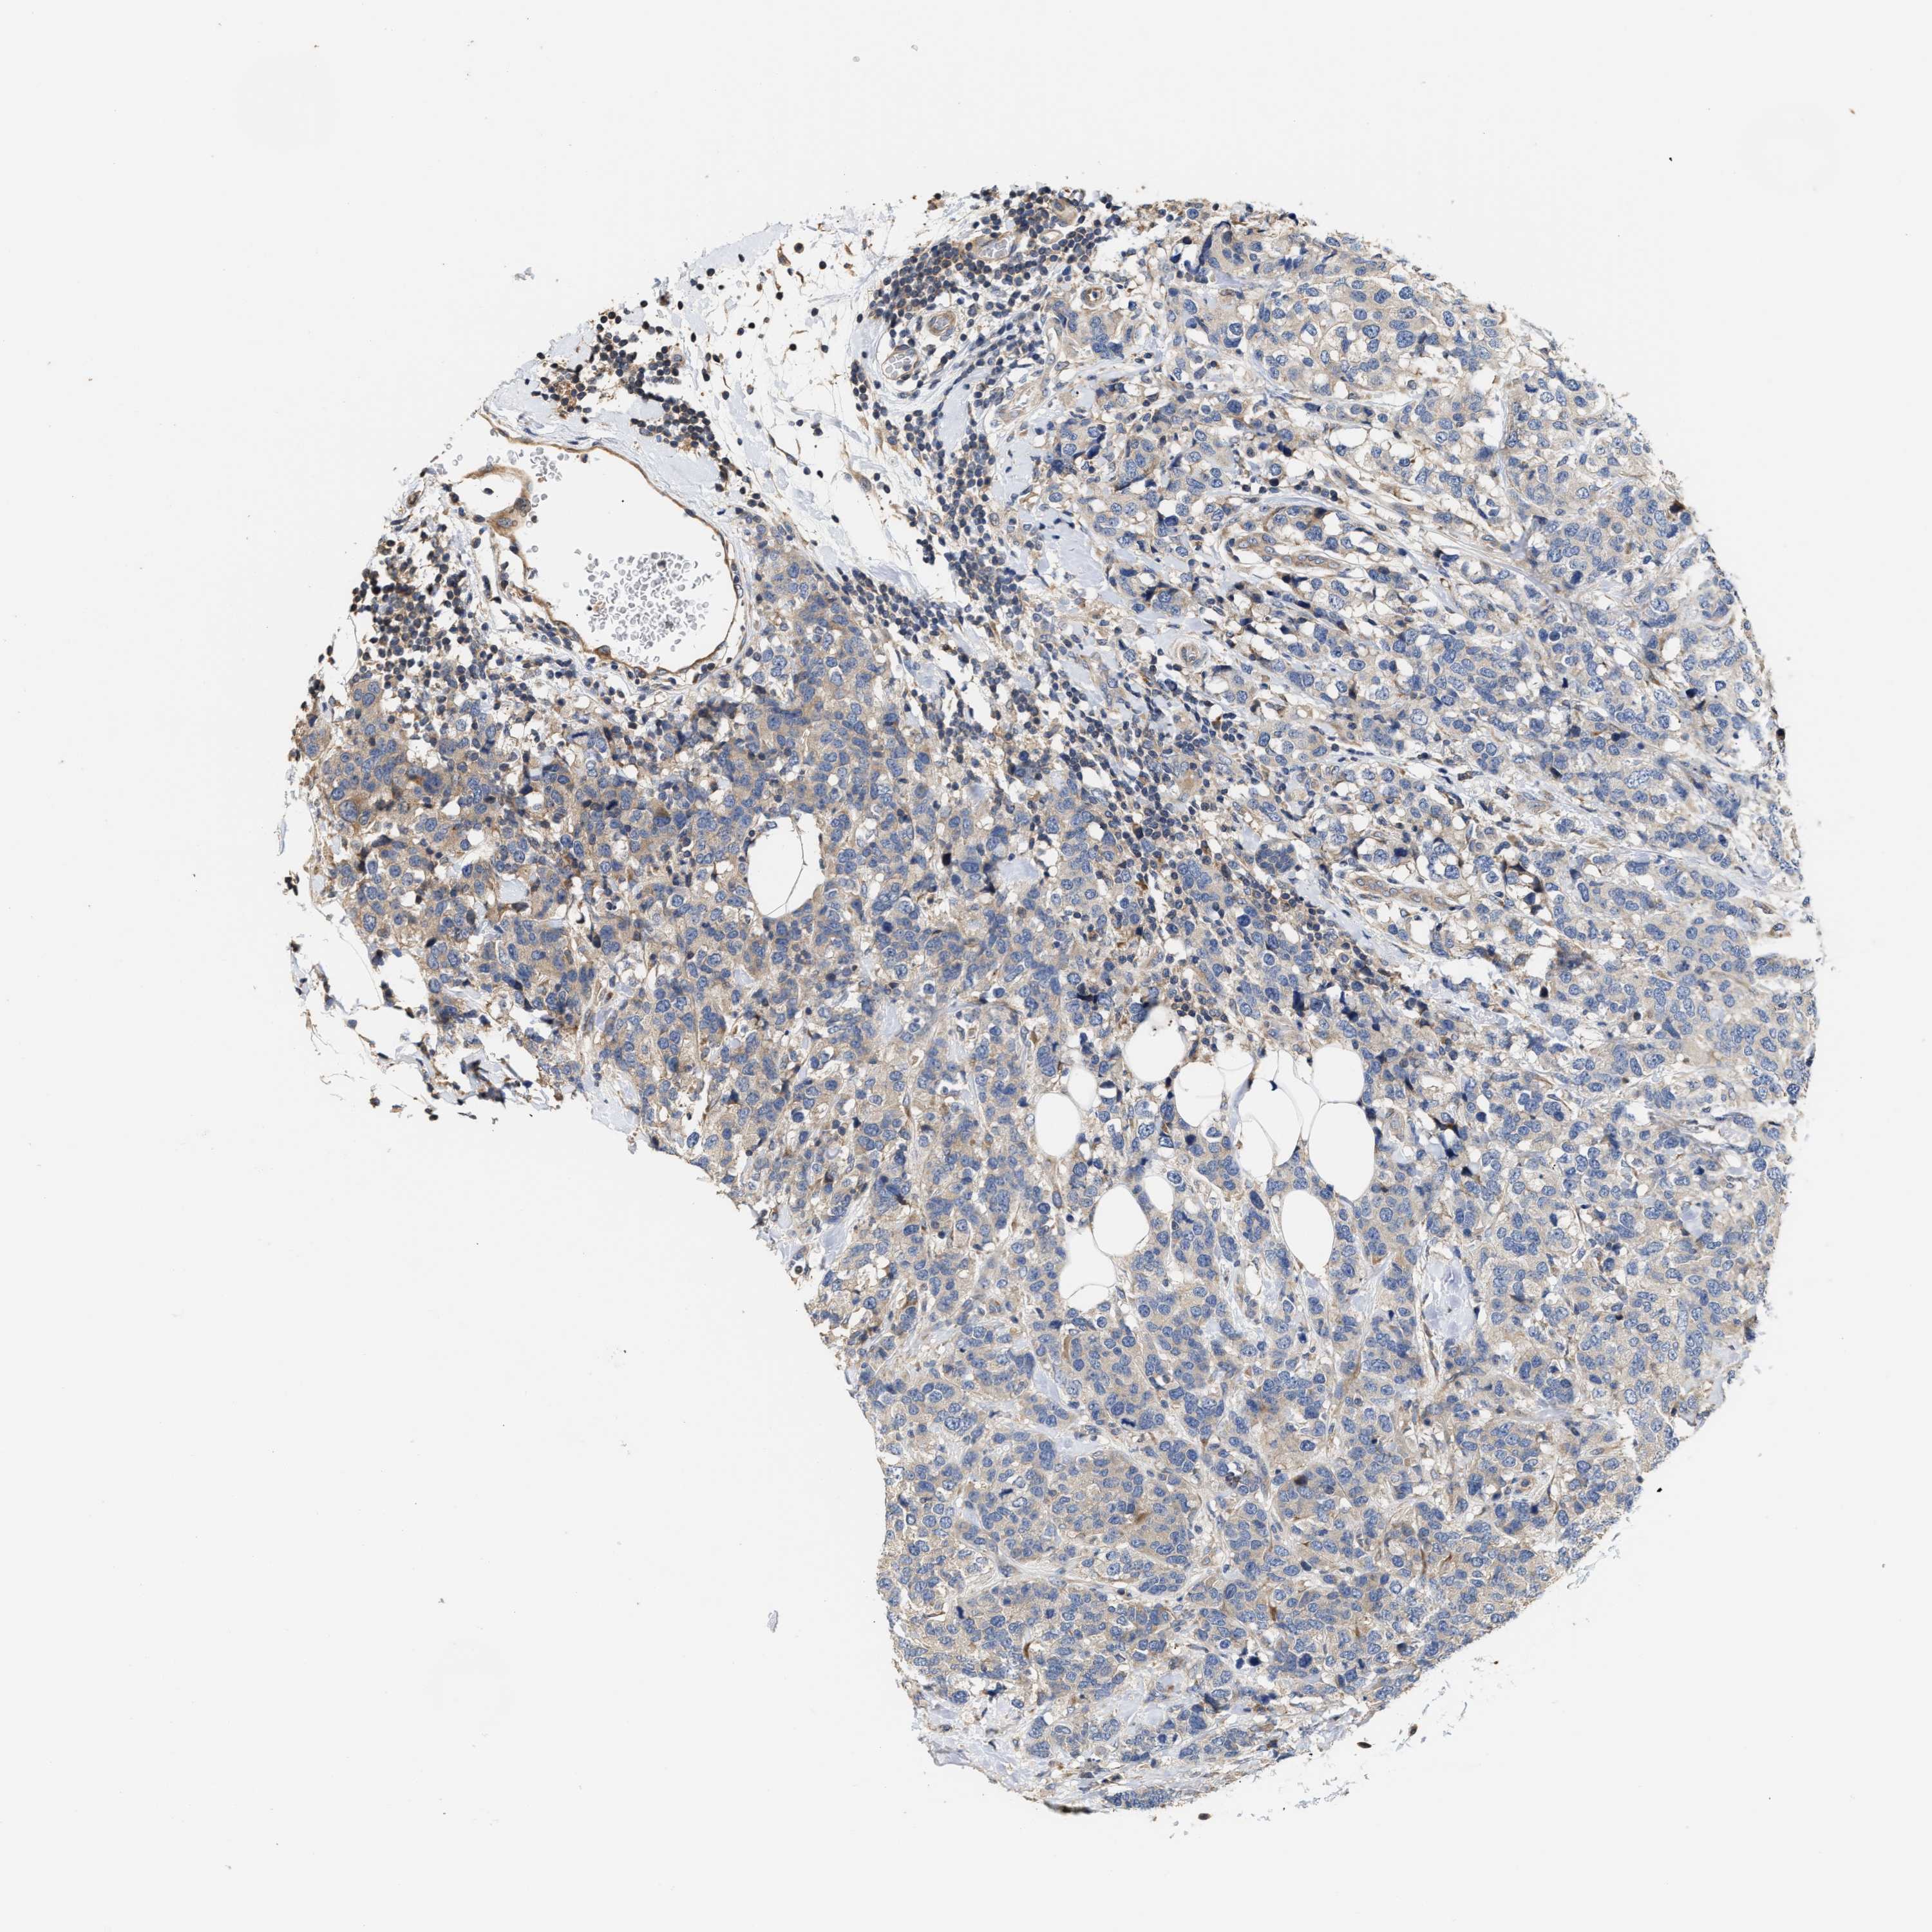

CANCER BREAST CANCER Show tissue menu

BRCA TCGA BRCA VALIDATION PROTEIN EXPRESSION